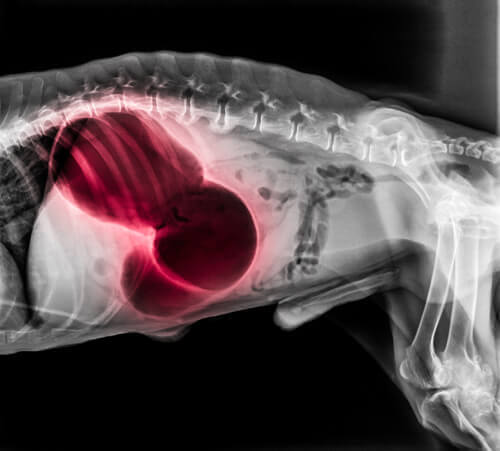

Blodprop i hjertet eller lungerne

En blodprop i hjertet eller lungerne kan medføre en række af alvorlige, systemiske symptomer, inklusiv besvimelse, stakåndethed og paralyse. Desuden, kan hundens gummer blive blege eller blålige, og den kan have svært ved at sove. Den kan også begynde at hoste blod op. Lungeemboli er, som regel, dødbringende.